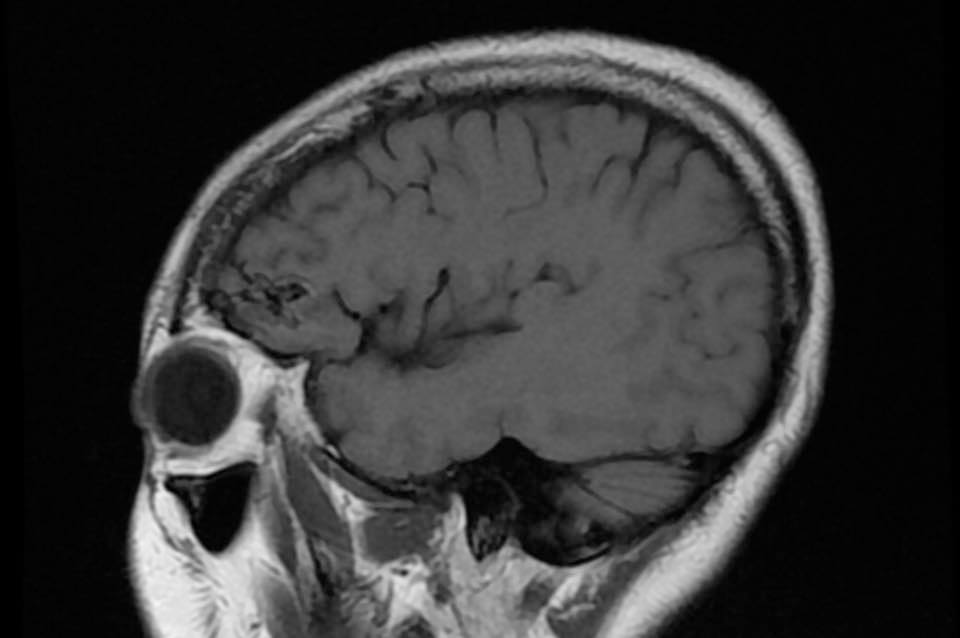

病人….被另一名曾經嚴重腦出血性中風(腦動脈瘤破裂以致嚴重的蜘蛛綱膜下腔出血及曾經瞳孔放大和深度昏迷…其後完全康復)的病人介紹…..帶MRI 底片到我診所尋求第二醫療諮詢….. 其時心情亦愉快…….直到….看了MRI 影像後…..我告訴她真正的MRI檢查結果……她的左前腦額葉上….有一個3cm大的腦動靜脈畸形血管瘤(AVM).. ….亦有最近出過血的跡象…可能是她失去意識和腦癇症的原因。

兩天後….在私家醫院為她做診斷式的動態腦血管造影來確定䐉血液的流動模式後,再進行了4 小時的顯微鏡手術….AVM的計時炸彈完全切除……..在AVM旁邊的腦部亦能看到血鐵黃素的舊有殘留血液。手術後兩天出院。